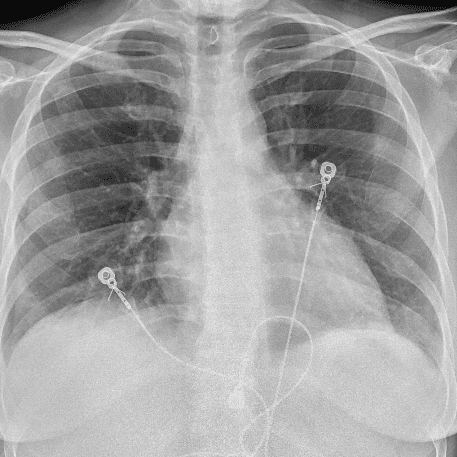

Practice Cases